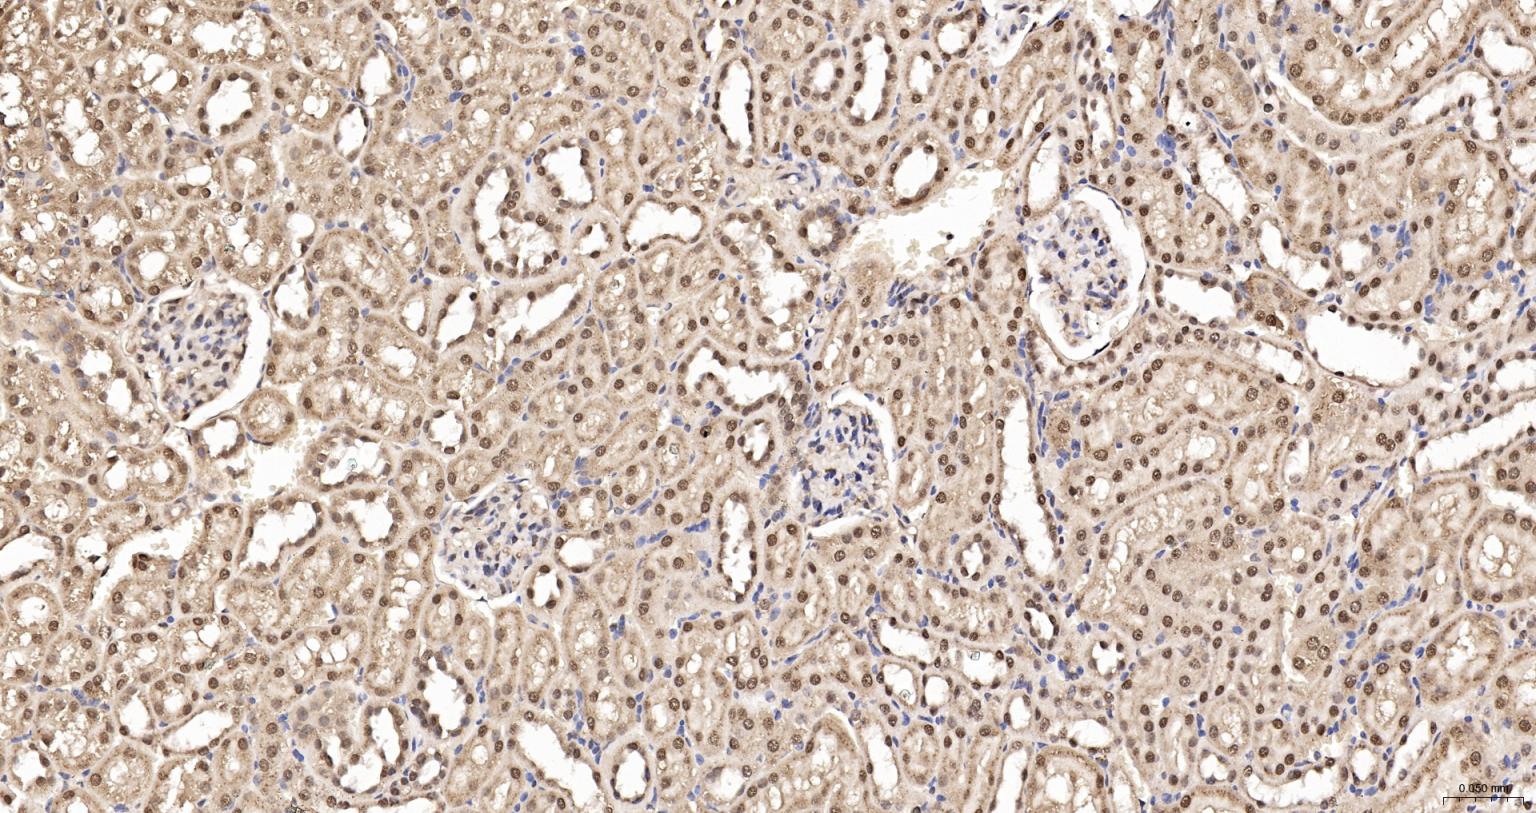

Paraformaldehyde-fixed, paraffin embedded Mouse Kidney; Antigen retrieval by boiling in sodium citrate buffer (pH6.0) for 15 min; The section was incubated with HDGF Monoclonal Antibody, Unconjugated (bsm-62928R) at 1:200 overnight at 4°C, followed by conjugation to the bs-0295G-HRP and DAB (C-0010) staining.

Paraformaldehyde-fixed, paraffin embedded Human Kidney; Antigen retrieval by boiling in sodium citrate buffer (pH6.0) for 15 min; The section was incubated with HDGF Monoclonal Antibody, Unconjugated (bsm-62928R) at 1:200 overnight at 4°C. Followed by conjugated Goat Anti-Rabbit IgG antibody (Red, bs-0295G-BF594), DAPI (blue, C02-04002) was used to stain the cell nuclei.